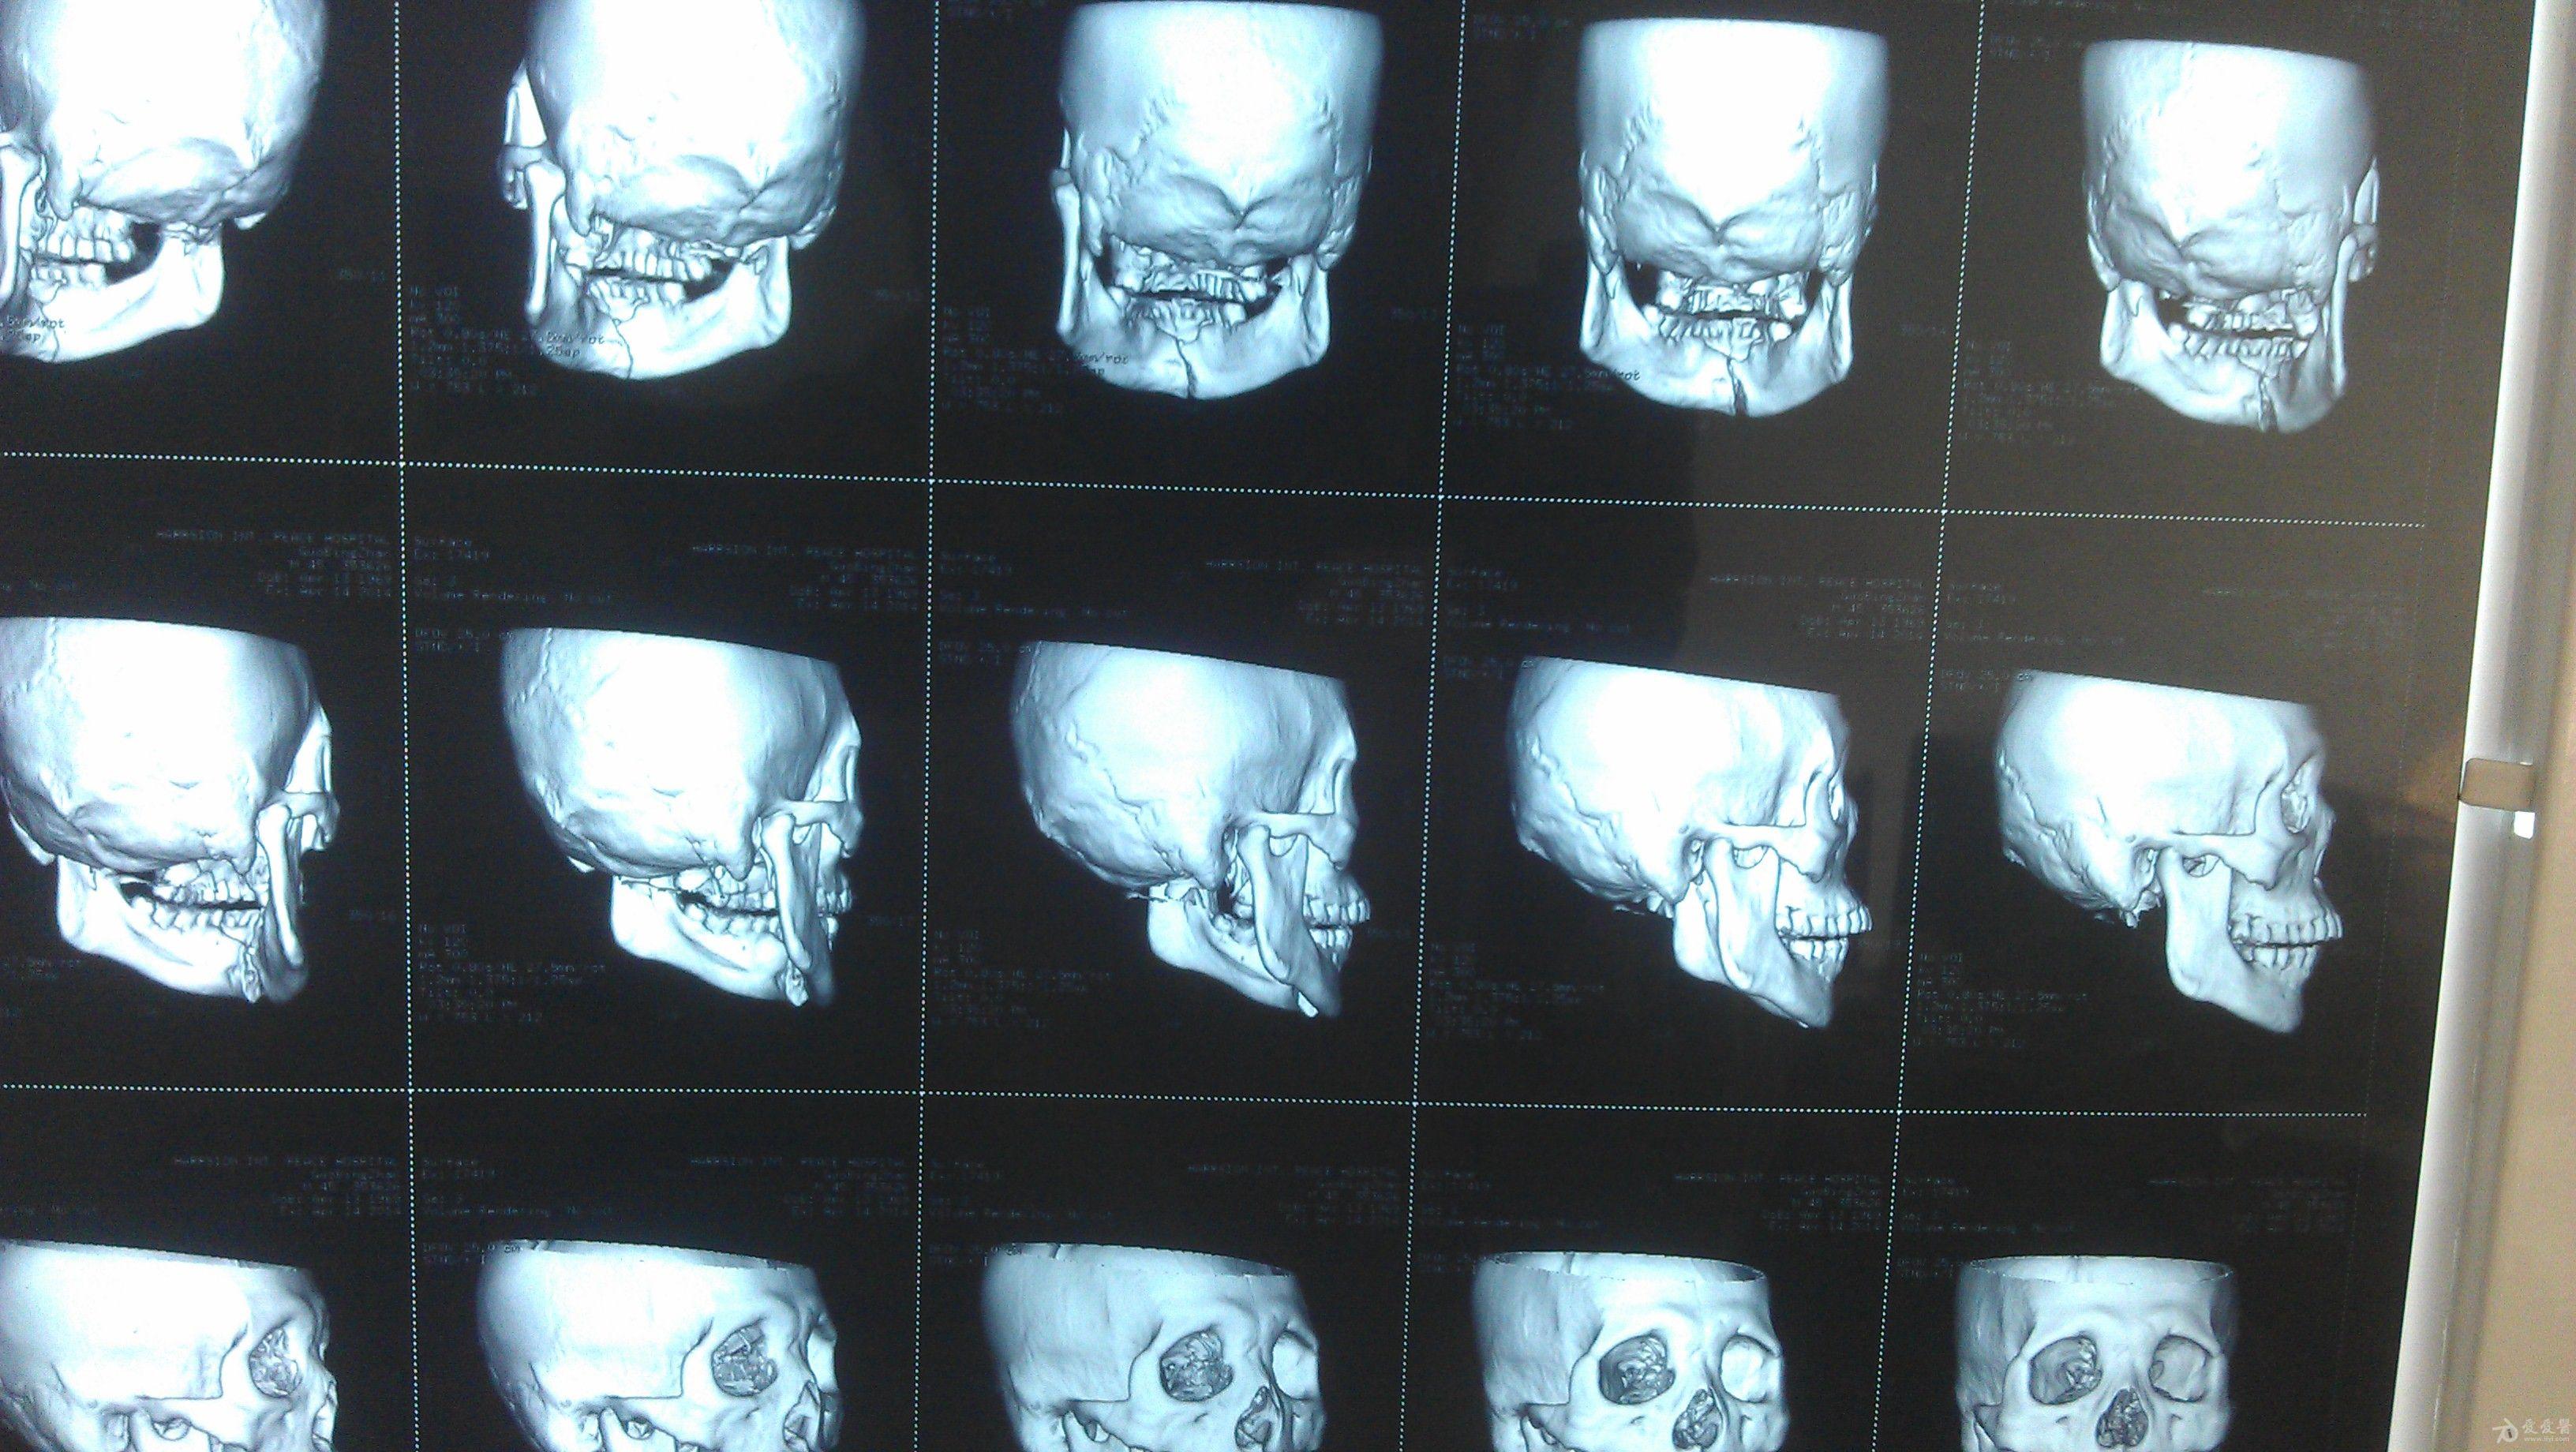

下颌骨骨折手术

一病人下颌骨骨折,合并其他骨折,行动不便,转院困难,现居乡镇,求治疗方案

我们这里没有专业口腔科医生可以做下颌骨骨折,如果骨科大夫做有什么需要注意的大夫,下颌骨钢板内固定治疗完成后还需要保持咬盒吗?还是直接捆牙槽弓加皮筋

此病人是下颌骨中正联合部斜向骨折伴牙槽骨骨折,但由于片子太小无法看清牙齿情况,如果牙齿受损需进行牙齿的相关治疗,骨折情况可行口内切口在保证正常咬合的基础上进行钢板固定,术后可行颌间结扎或牵引。